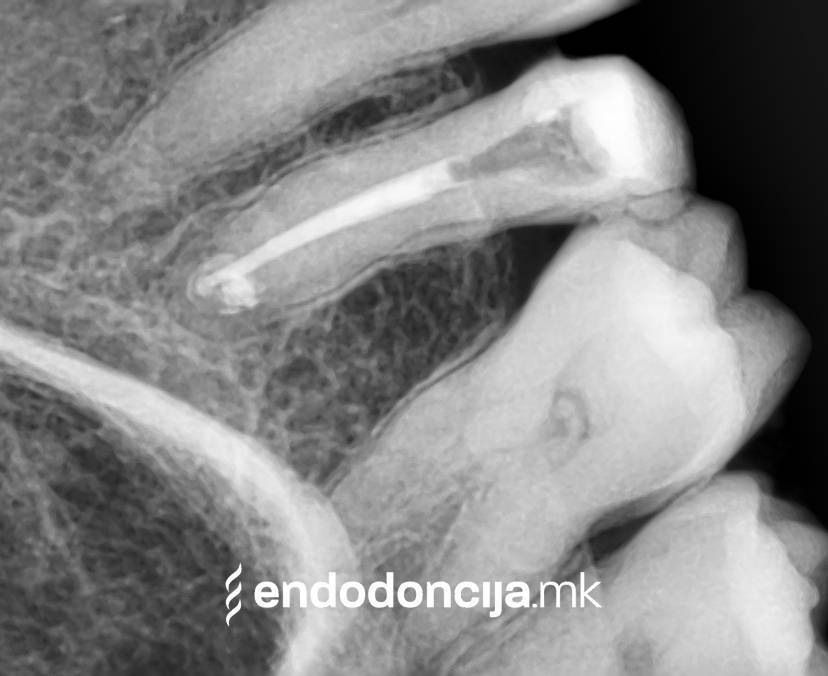

Κατά τη διάρκεια της επεξεργασίας του ριζικού σωλήνα, τα λεπτά όργανα ενδέχεται να σπάσουν. Αυτό μπορεί να αποτελέσει εμπόδιο για την πλήρη προετοιμασία και τον καθαρισμό του ριζικού σωλήνα. Με μια μικροσκοπική επεξεργασία του ριζικού σωλήνα μπορεί να είναι δυνατή η απομάκρυνσή τους υπό ορισμένες συνθήκες, χωρίς να καταστρέφεται η ουσία των δοντιών.